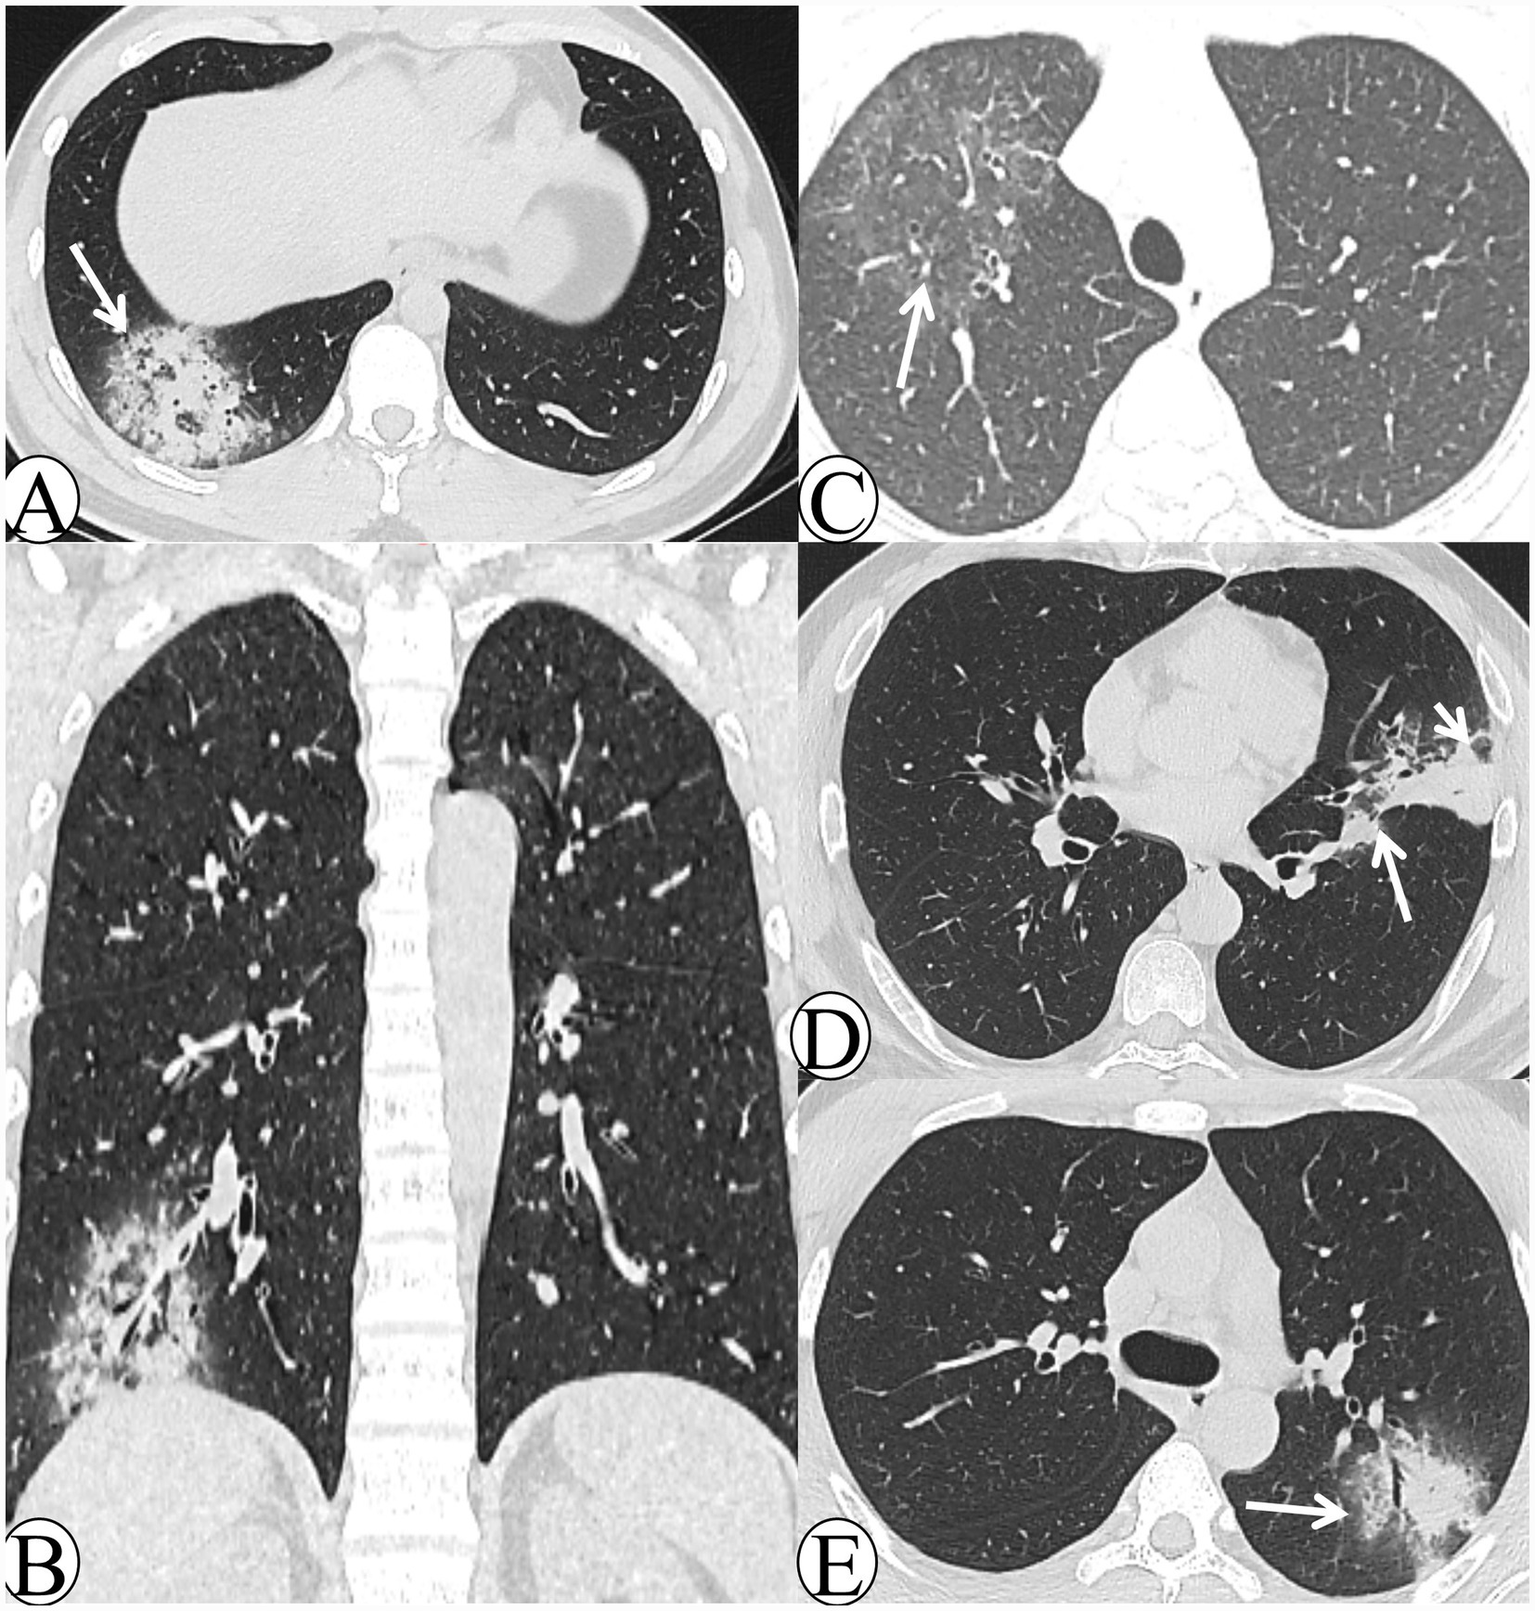

Chest CT manifestations in the early-stage group included: 5 cases (17.2%) with a lobar pneumonia pattern (Figure 1A), 16 cases (55.2%) with a lobular pneumonia pattern (Figure 1B), and 8 cases (27.6%) with a nodular–patchy pattern (Figures 1C,D). With respect to lobe involvement, 20 cases (69.0%) exhibited single-lobe involvement, whereas 9 cases (31.0%) demonstrated multi-lobe involvement. In terms of lesion distribution, 10 cases (34.5%) were predominantly located in the upper lobes, whereas 19 cases (65.5%) were primarily in the lower lobes; no cases demonstrated diffuse involvement. Regarding ancillary signs, 25 cases (86.2%) exhibited the halo sign, whereas only 1 case (3.4%) exhibited the reversed halo sign. Centrilobular nodules were observed in 23 cases (79.3%), and bronchial wall thickening in 20 cases (69.0%). Additionally, lobular sparing (Figure 1E) was present in 19 cases (65.5%), the reversed tree-in-bud sign (Figure 1F) in 17 cases (58.6%), and the tree-in-bud sign in 14 cases (48.3%). Interlobular septal thickening (Figure 1E) was noted in 3 cases (10.3%), and intralobular septal thickening (Figure 1F) in 1 case (3.4%). No necrosis or cavitation was detected in any patient.

Figure 1

The CT images of early-stage Chlamydia pneumoniae pneumonia. (A) A 24-year-old male patient presented with fever, productive cough, and headache persisting for 5 days. Axial lung window CT demonstrates extensive consolidation in the right lower lobe with an air bronchogram (white arrow) and a visible peripheral halo sign. (B) A 21-year-old male patient presented with fever, pharyngeal hyperemia, and myalgia persisting for 6 days. Axial lung window CT demonstrates bronchial wall thickening in the left lower lobe, accompanied by patchy consolidation and ground-glass opacity (GGO), together with distal tree-in-bud and centrilobular nodules (white arrow). (C) A 21-year-old male patient presented with chills and fever for 1 day. Axial lung window CT demonstrates a round-like patch in the left upper lobe, accompanied by an air bronchogram and surrounding ill-defined centrilobular nodules (white arrow). (D) A 16-year-old male patient presented with cough and expectoration for 5 days. Axial lung window CT demonstrates multiple mass-like and nodular-patchy consolidations with a halo sign in the right upper lobe (white arrow). (E) A 45-year-old female patient presented with chills and fever for 5 days. Axial lung window CT demonstrates peribronchial patchy consolidation and ground-glass opacity (GGO) in the right lower lobe, with visible interlobular septal thickening and lobular sparing (white arrows). (F) A 29-year-old male patient presented with fever and cough for 4 days. Axial lung window CT demonstrates patchy consolidation and ground-glass opacity (GGO) in the right upper lobe, with visible intralobular septal thickening (white arrowhead) and a reversed tree-in-bud sign (white arrow).